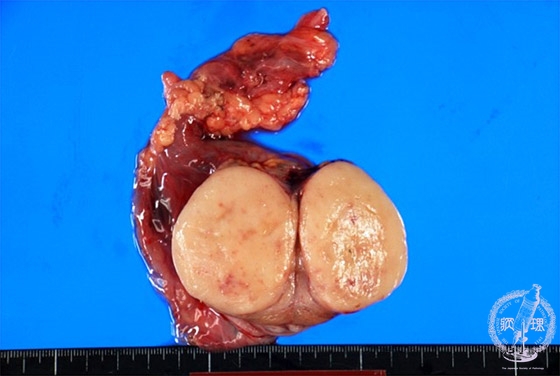

- ★(4)Seminoma (Germ cell tumor)

Macroscopic appearance: Seminoma. Soft and well marginated pale to yellow tumor with bulging cut surface (yellow dotted line). Unless other types of germ cell tumors coexist, hemorrhage or necrosis is rarely found.